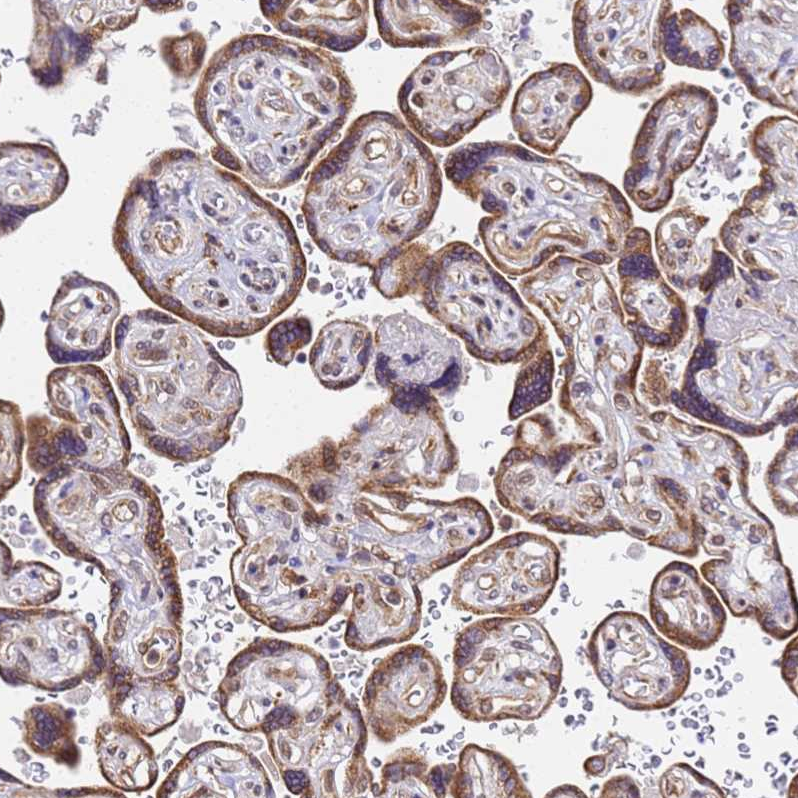

Immunohistochemical staining of human lung shows strong cytoplasmic positivity in macrophages.